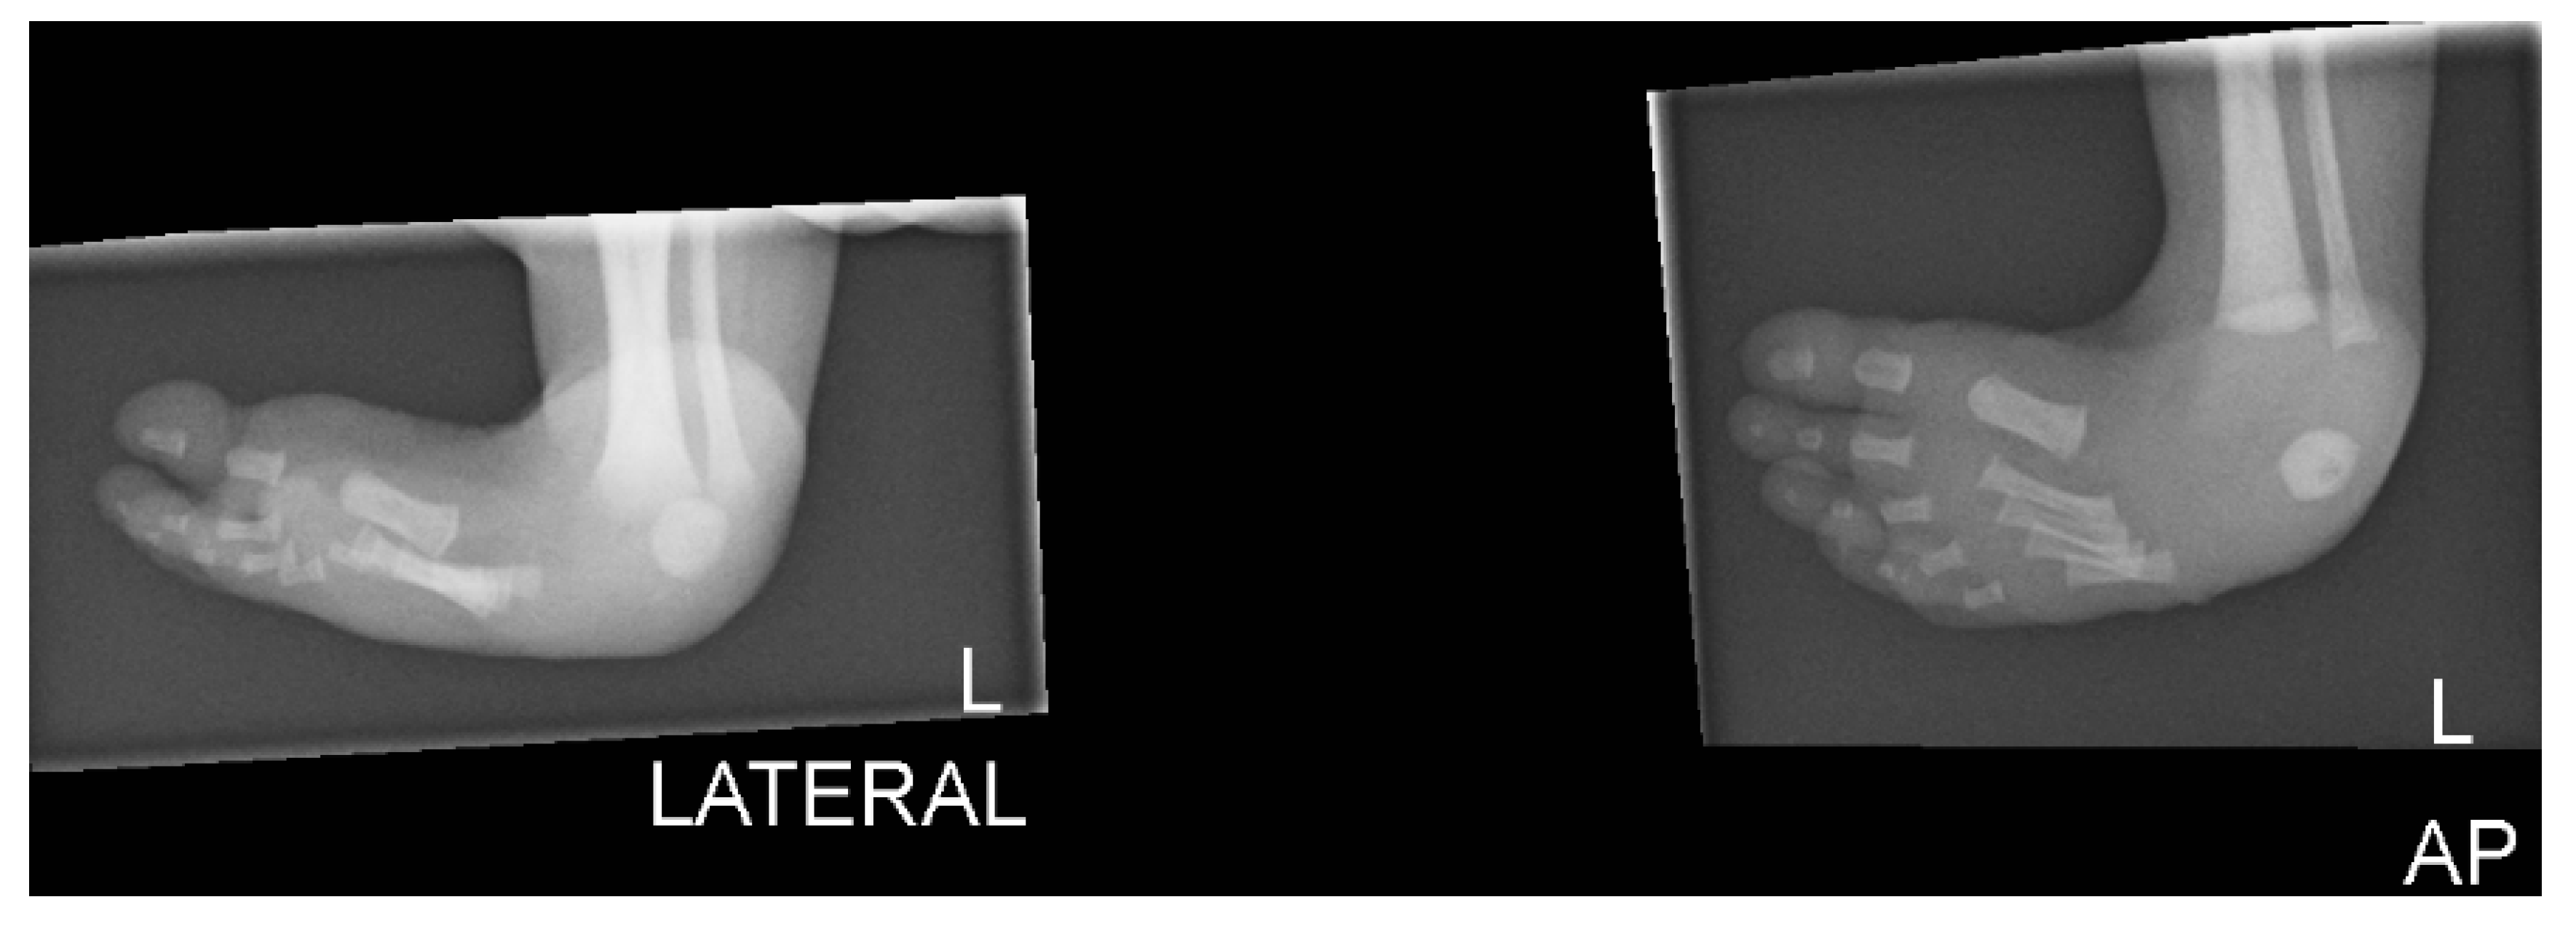

2. Case Presentation